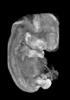

Carnegie Stage 19 (47 post-ovulatory days)

About Carnegie Stage 19

Most embryos at stage 19 are approximately 47-48 post-ovulatory days old and measure 17-20 mm in length. Distinguishing criteria for this stage include straightening of the trunk, the limbs extend nearly directly forward, toe rays are prominent, but interdigital notches have not yet appeared in the foot.

Although some of the photographs below show abnormal embryos, the animations and MRI slice images all depict normal embryos. Abnormal embryos are noted in the titles of the large photos when they are opened.